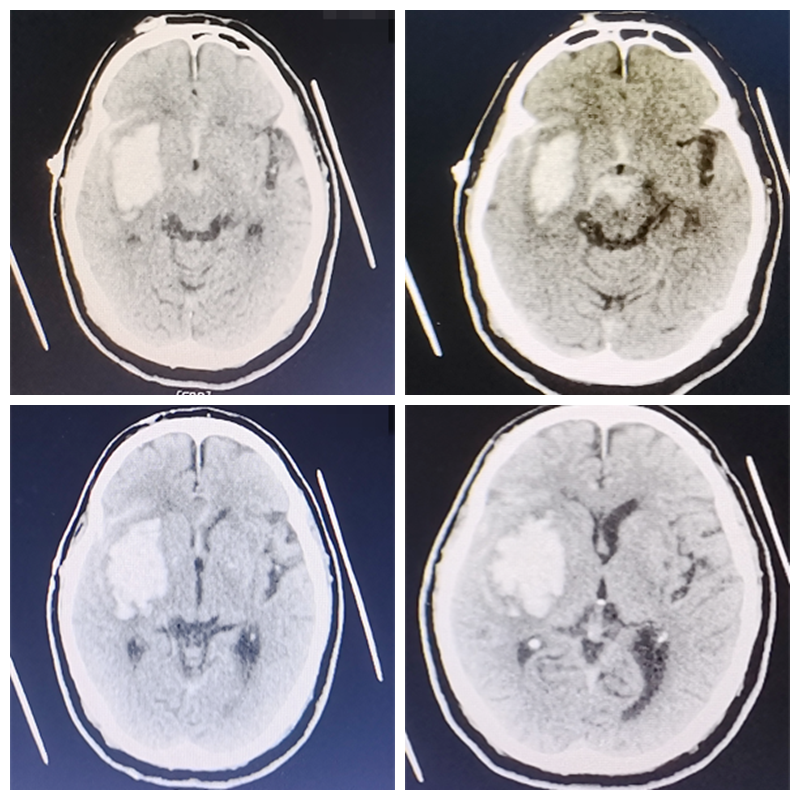

76岁的古大爷因“突发左侧肢体乏力伴言语不清3小时余”入院,进行头颅CT检查示“右侧基底节区、岛叶急性脑出血”收住我院神经外科一区,我科主任杨建雄、副主任医师郑达理手术团队进行术前讨论:如果选择以往的开颅去骨瓣减压治疗手术,不但切口大、时间长,而且会对周围脑组织造成较大的损伤,患者家属担心老人能否承受开颅手术;除此之外,在局麻下行脑内血肿穿刺置管引流术,可能存在血肿清除效果缓慢,且引流不彻底等情况,一旦出血增加,需要再次选择开颅手术,造成不可逆的损伤。

▲术前颅脑CT